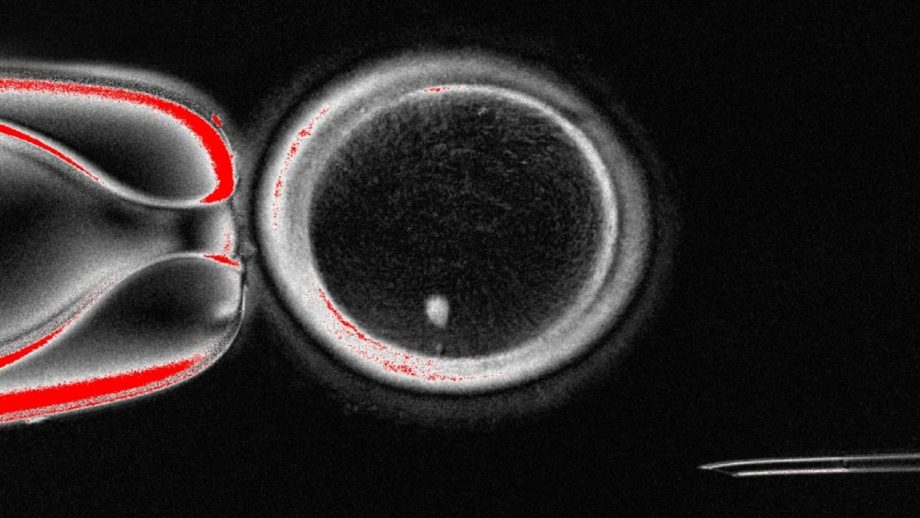

Researchers at Oregon Health & Science University (OHSU) have developed a proof of concept that turns skin cells into eggs capable of producing early human embryos.

The advance offers a potential new path for treating infertility through in vitro gametogenesis, the process of creating eggs and sperm outside the body.

Instead of reprogramming stem cells into gametes, the scientists used somatic cell nuclear transfer, the same basic approach that cloned Dolly the sheep in 1997.

They transplanted the nucleus of a skin cell into a donor egg stripped of its own nucleus. The donor egg’s cytoplasm triggered the skin cell nucleus to discard half its chromosomes, mimicking meiosis.

The result was a haploid egg that could then be fertilized with sperm through standard IVF, forming embryos with equal genetic input from both parents.

In the study, researchers generated 82 functional oocytes and fertilized them with sperm. While most stalled at the 4- to 8-cell stage with chromosomal abnormalities, about 9 percent developed to the blastocyst stage six days after fertilization.